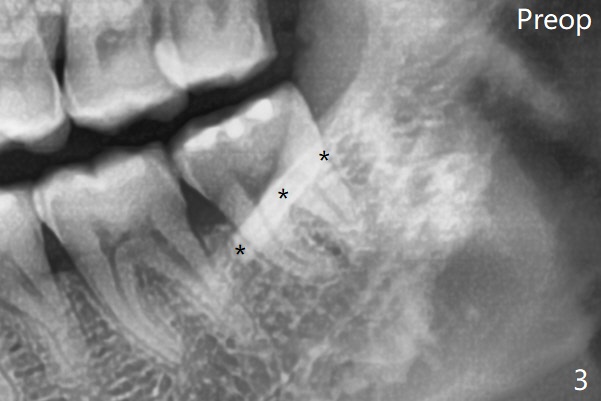

Since no buccal trough is made for extraction, the external oblique ridge (*) is present at #17 and 32 before and after surgery. Bond Apatite is placed with Collagen Plug (Fig.7).